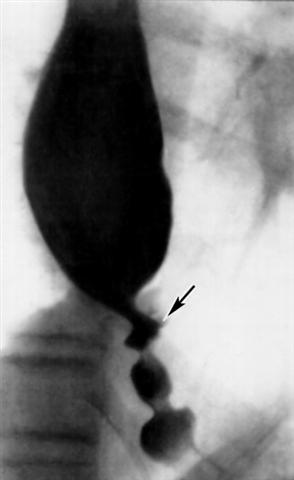

Рис. ж). Рентгенологическая картина при различных заболеваниях и поражениях пищевода, сопровождающихся дисфагией: рефлюкс-эзофагит, осложненный склерозом и изъязвлением (указано стрелкой) стенки пищевода.